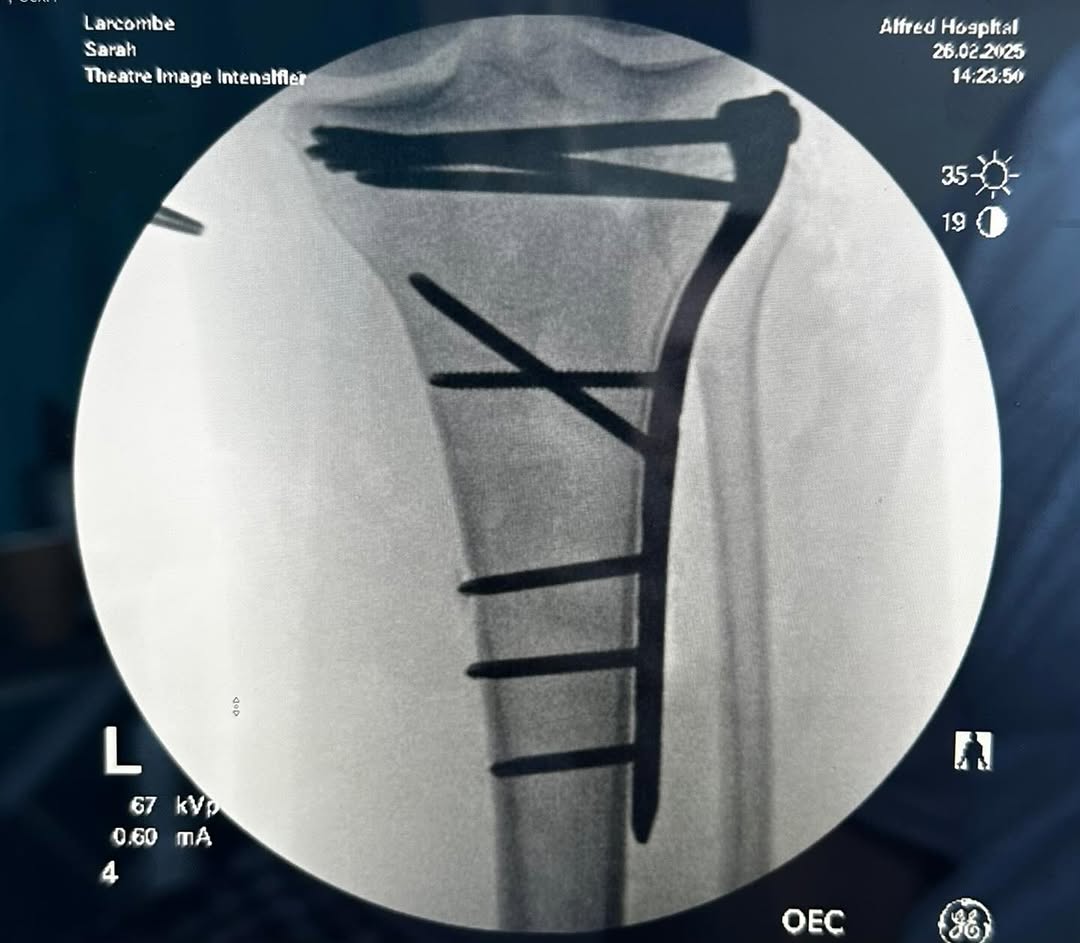

After two nights in Horsham, she was flown to The Alfred in Melbourne on the Tuesday, went under the knife to have plates and pins put in her knee the following day and was discharged two days later to start her rehabilitation journey.

Larcombe's left tibia was broken up near her knee. (Supplied: Sarah Larcombe)